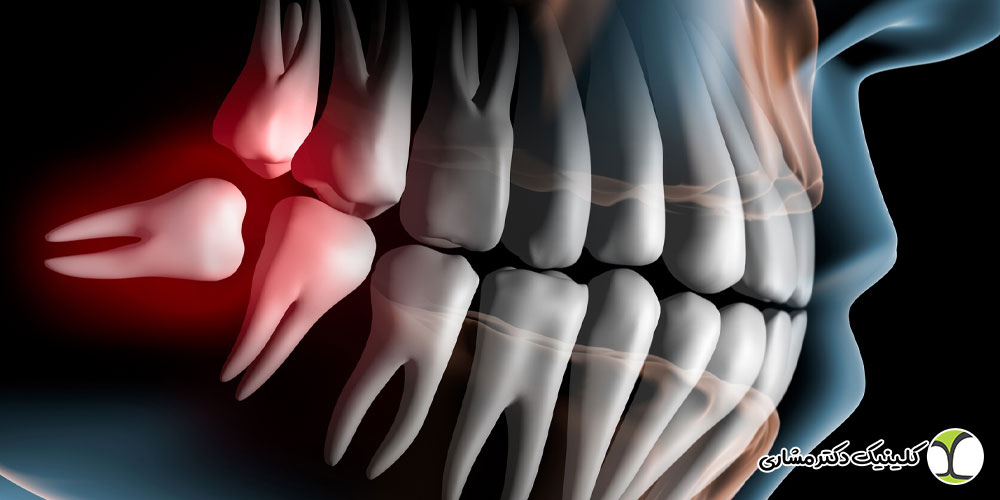

- موقعیت مکانی: قرارگیری دندان عقل در انتهای فک، دسترسی دندانپزشک را برای درمانهای معمولی، از جمله درمان ریشه، دشوارتر میکند.

- ساختار ریشه: ریشههای دندان عقل اغلب دارای شکلهای منحنی یا غیر منظم بوده و تعداد و ساختار کانالهای عصبی میتواند پیچیدگی بیشتری نسبت به سایر دندانها داشته باشد.

- رشد نامناسب: دندان عقل ممکن است به صورت نیمهنهفته (بخشی از آن زیر لثه مانده) یا کاملاً نهفته (داخل استخوان فک) رشد کند، که این شرایط معمولاً عصبکشی را غیرممکن یا بیفایده میسازد.

- تصمیم نهایی برای حفظ: درمان ریشه دندان عقل زمانی مطرح میشود که دندان در موقعیت مناسبی قرار گرفته، عملکرد خود را به درستی انجام میدهد و پتانسیل نگهداری را داشته باشد، اما عفونت پالپ (عصب) به دلیل پوسیدگی عمیق یا ضربه، سلامت آن را به خطر انداخته است.